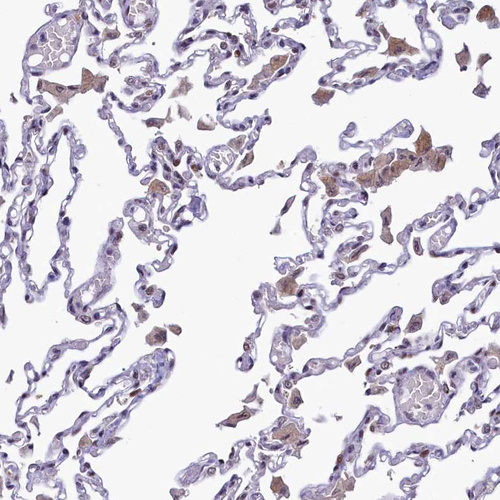

Immunohistochemical staining of human Kidney shows moderate cytoplasmic positivity in cells in tubules.